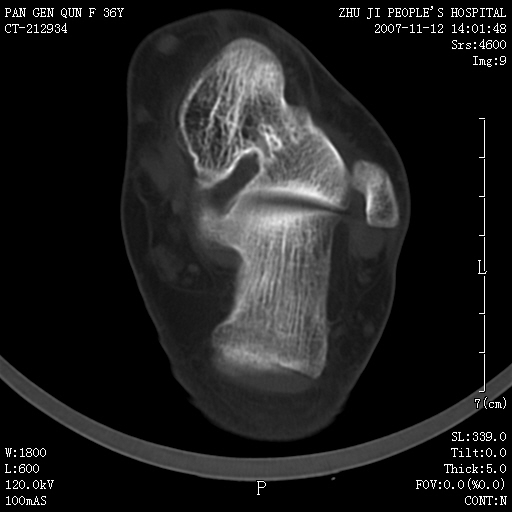

标题: CT10417:F36Y,跟骨跟腱附着处下方骨质密度影,请会诊. [打印本页]

标题: CT10417:F36Y,跟骨跟腱附着处下方骨质密度影,请会诊.

跟骨结节后部肿块半年,无明确外伤史,及红肿热痛.

如果是骨瘤,也应该是骨旁骨瘤。发生部位不支持骨瘤,骨肿瘤提倡临床、放射、病理三结合诊断。